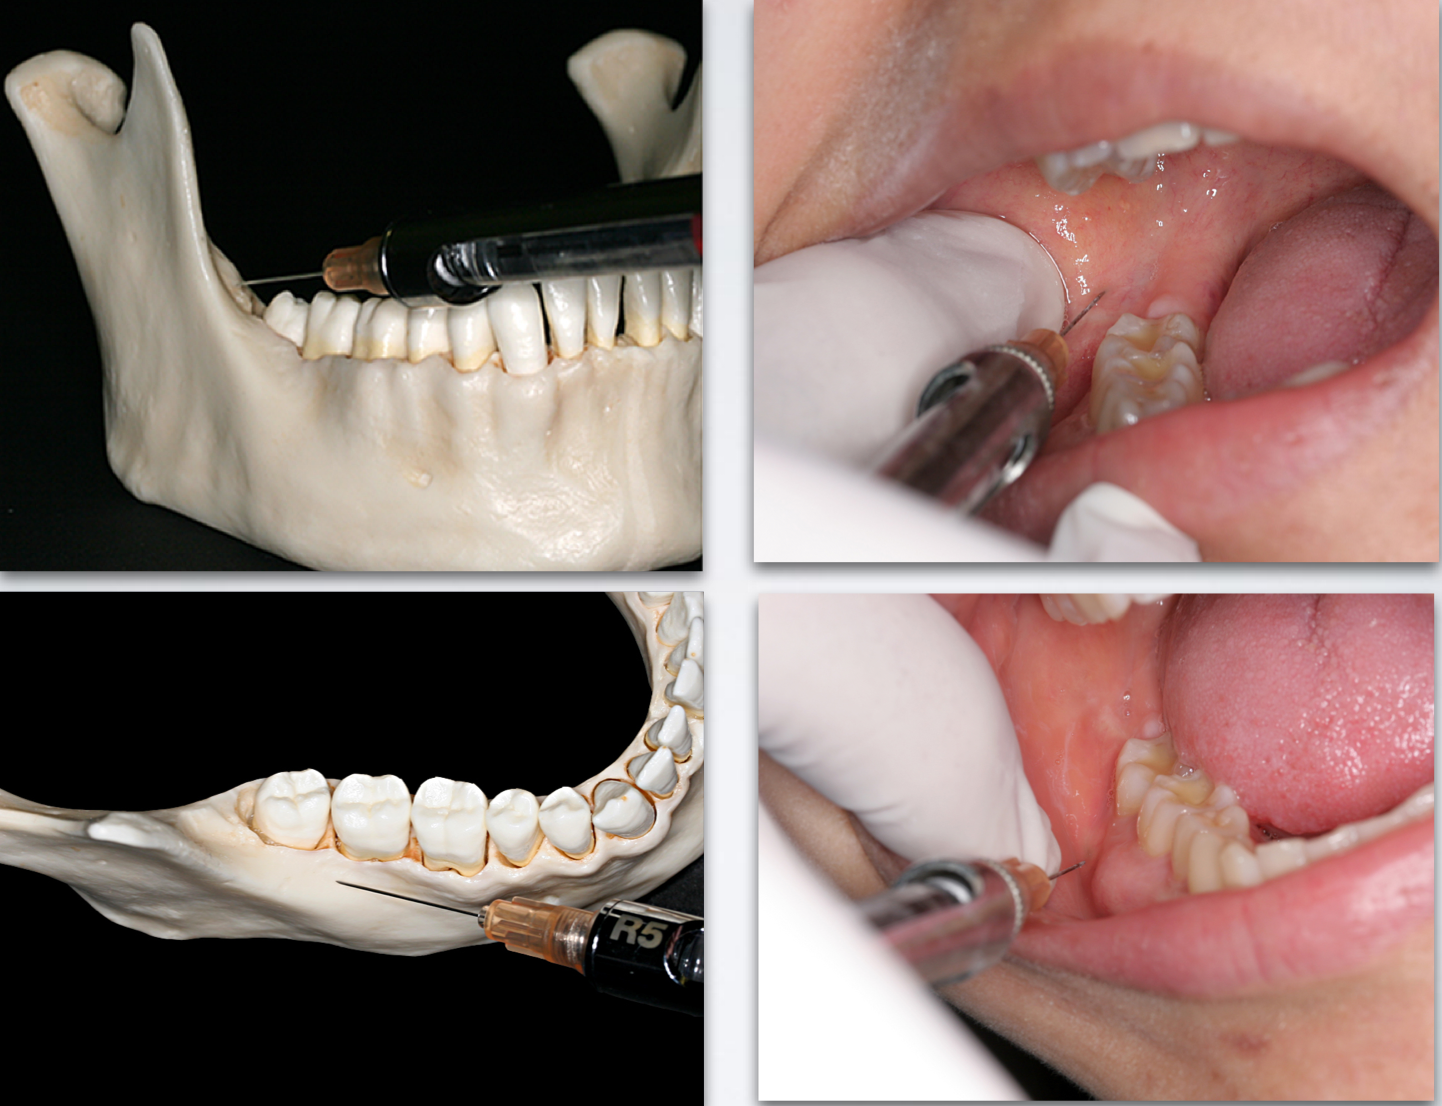

Use 25 gauge long needle

Retract the tongue

Direct the syringe from the opposite side

Direct needle tip to the apical region of the tooth immediately posterior to the tooth in question, until bone is contacted

Aspirate and deposit ~0.6 ml of solution

mylohyoid nerve block